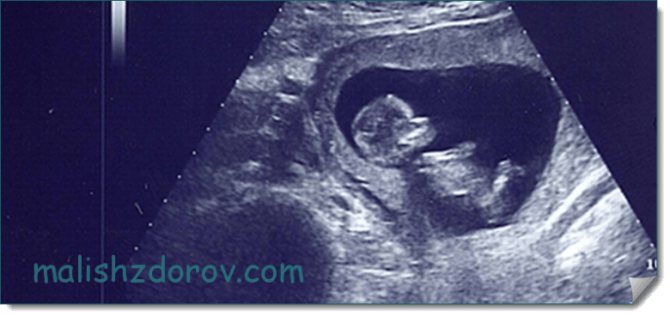

Фото ребенка на УЗИ

На фото можно увидеть, как выглядит плод на УЗИ